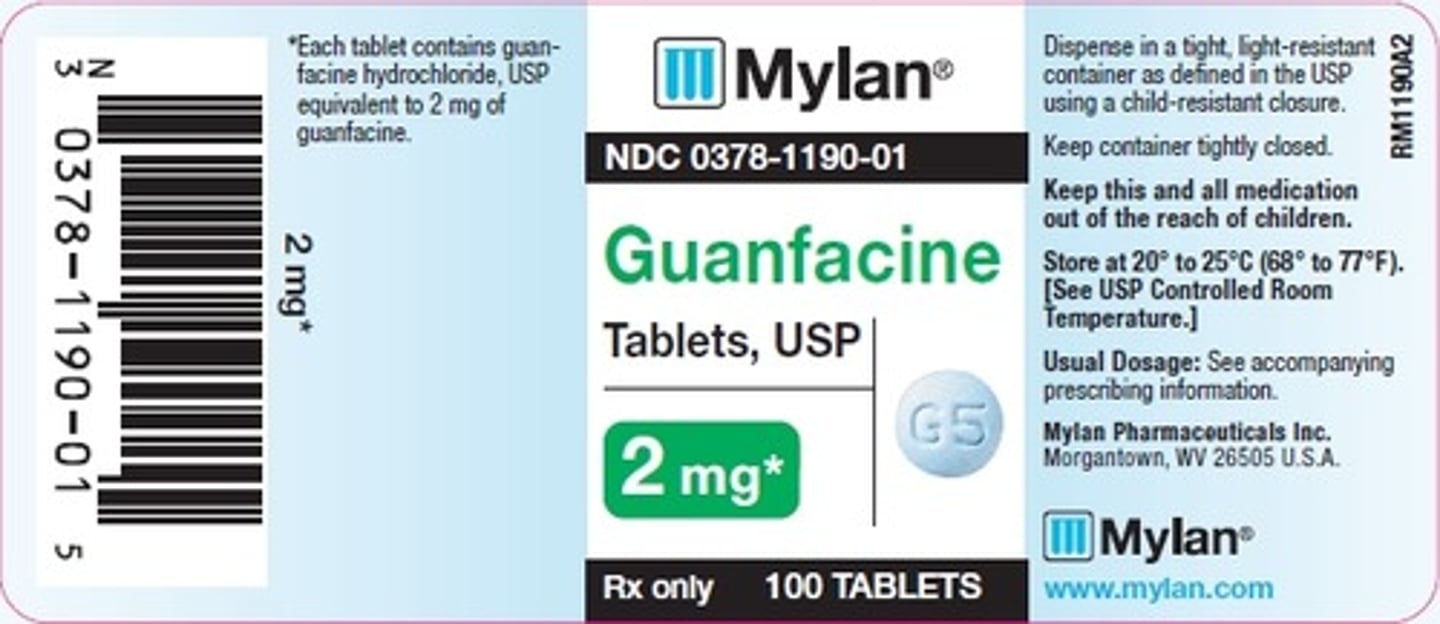

Guanfacine

Brand: Tenex

Class: Alpha-2 Agonist

Indication: ADHD, Antihypertensive

Schedule: NCLM